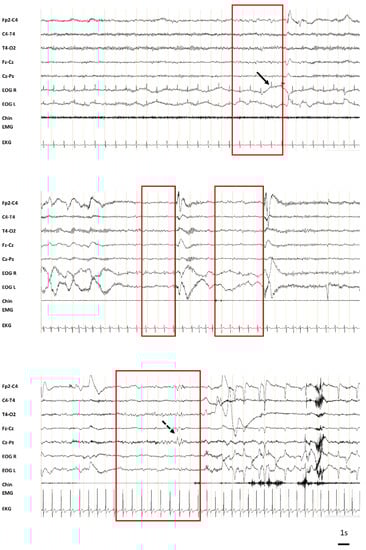

- The occurrence of one or more MSs during the entire test (in case the patient did not fall asleep) or until sleep onset. MSs were defined by the appearance of theta or delta waves with a disappearance of alpha in the absence of eye opening, sometimes associated with slow eye movements, lasting from 3 to 15 s. The latency, duration, number, and EEG description of the MSs were collected. In the absence of MS, the sleep latency considered for the test was SOL (or 40 min in the absence of sleep).